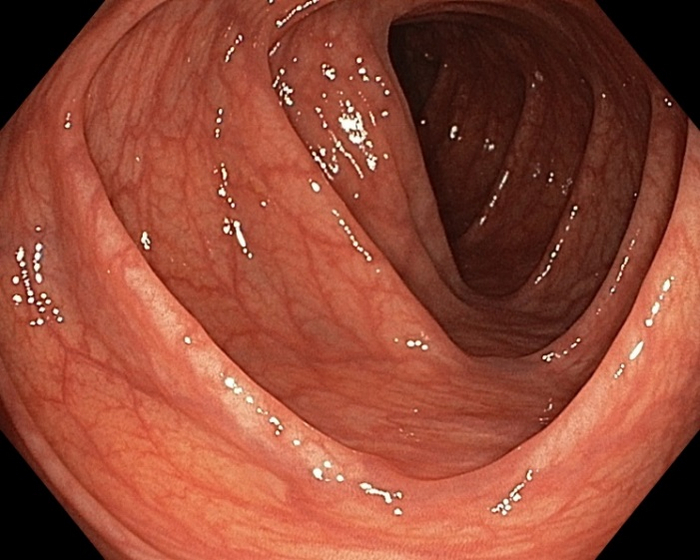

Кабинет колоноскопии выглядит вот так, кушетка очень маленькая, чем-то напоминает гинекологический либо урологический операционный стол.

Раздеваешься по пояс, ложишься на левый бок, тебе вводят в анус пальцем, после чего вводят эндоскоп, в который встроена подача воздуха и воды, как у стоматологов.

Сначала совершенно не больно, но когда врач проходит ободочную кишку, хочется плакать, дело в том, что она устроена не так. как остальной кишечник и имеет ямки и высокие бортики, хз , как называются, вот их очень тяжело проходить.

Теперь главное - у меня все получилось, по моей схеме питания кишка выглядела идеально, без пены и без какашек.

Во время исследования лучше дышать животом почаще, особенно когда идет накачка воздухом либо врач проворачивает эндоскоп, чтобы осмотреть противоположную стенку. Исследование заняло 20 минут, меня 2 раза переворачивали на спину, т.к. злосчастная ободочная кишка скрывалась от исследователя. Лишь в верхнем отделе кишечника ближе к желудку было небольшое количество раствора, который не вышел утром во время дефекации, он не помешал провести исследование.

Всем удачных исследований, и помните, что ответственность за подготовку возлагается полностью за пациента, и если у вас будет что-то типа такого, то деньги вам не вернут, а только зайдут, посмотрят, и выйдут.